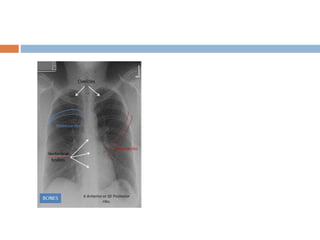

Approach to CXR

 Airway

 Bones and soft tissue

 Cardiac

 Diaphargm

 Effusions

 Fields (lung)

 Gastric

 Hila and mediastinum